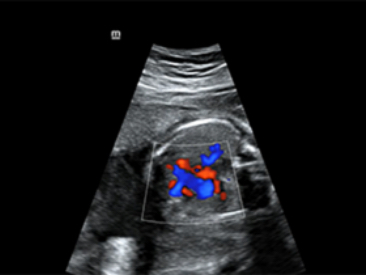

SC5-1N ve SD8-1E

SC5-1N ve SD8-1E

Klinik G?rĂŒntĂŒler